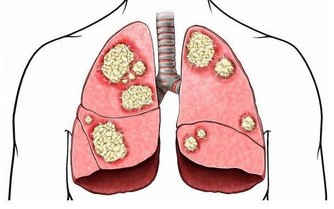

近一個月前,年僅27歲韓國男藝人金宇彬宣布患鼻咽癌,引起一片嘩然。

最近,金宇彬所在的公司透露了他的治療近況:

因擔心手術可能造成腦部的後遺症,金宇彬選擇接受放射治療。

大家都知道,放射治療是一種通過對局部進行照射放射線的治療方法,是治療癌症的最常用的手段之一。